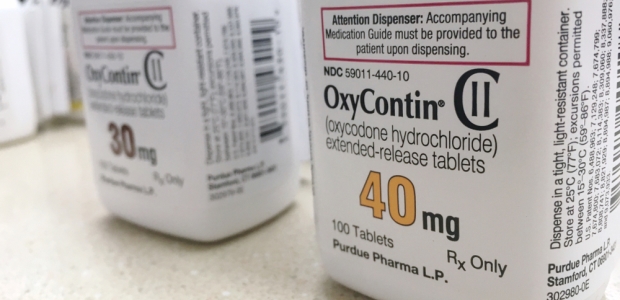

The Ohio Bureau of Workers' Compensation will no longer pay for Oxycontin or generic sustained-release oxycodone tablets for workers who suffer on-the-job injuries on or after June 1, 2019. Injured workers who are currently on those medications will have until Dec. 31 to discontinue their use or switch to a different product on the state agency's formulary.

"We need help from policy makers to ensure that more people have access to treatment. Physicians are responding to the epidemic and we are seeing results: a reduction in opioid prescribing of 33 percent since 2013, increased use of prescription drug monitoring programs, enhanced education, and greater co-prescribing of naloxone," said AMA President-elect Dr. Patrice A. Harris, who is the task force's chair. "But we cannot enforce parity laws or eliminate administrative barriers without the help of state and federal authorities, and that's what is limiting treatment now."